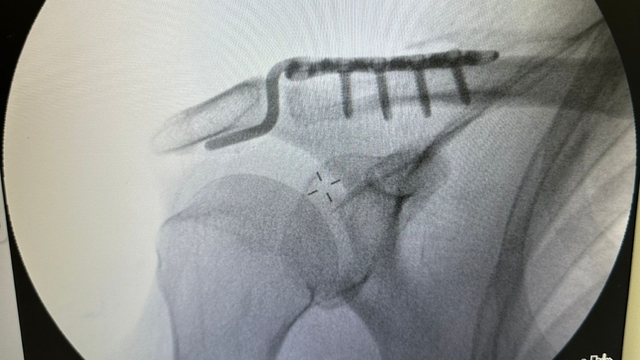

Kentteki bir kortta düştükten sonra omzunda çıkık oluşan Rençber’e, başvurduğu bazı merkezlerde yaş nedeniyle ameliyat önerilmedi. Batman Eğitim ve Araştırma Hastanesi Ortopedi ve Travmatoloji Uzmanı Dr. Mehmet Yavuz Başer’in değerlendirmesi sonrası hasta ameliyata alındı. Rençber’in omzuna kemik yapısına uyumlu, nadir kullanılan özel bir plak takıldı. Ameliyatın ardından fizyoterapi süreci başlatılan hasta, ağrılarının azalmasıyla günlük hareketlerini yapabilir hale geldi ve taburcu edildi.

Ameliyatın başarılı geçtiğini ifade eden Ortopedi ve Travmatoloji Uzmanı Dr. Mehmet Yavuz Başer, “Genelde gençlere ameliyat önerilirken bu hastamıza yaşından dolayı ameliyatlarla ilgili bazı sıkıntılar olduğu anlatılmış. Biz filmlerini gördük. Kendisiyle konuştuk. Muayenesini yaptık. Sosyal olarak aktif birisi olduğu için ameliyat kararını daha uygun gördük. Ameliyatı çok şükür güzel geçti, başarılı geçti. Nadir kullanılan bir plaktan kullandık. O da hastamıza tam olarak uydu. Hastamızın ameliyatı başarıyla geçti. Bundan sonraki süreci de hızlı bir şekilde eski haline kavuşturacağız inşallah 3 hafta içinde. Fizik tedavi sürecini başlattık. Şu anda birçok hareketi yapabiliyor. Biraz ağrıları geçince inşallah eski haline kavuşacak. Hastamızı bugün inşallah pansumanını ve tedavisini yaptıktan sonra taburcu edeceğiz” dedi.